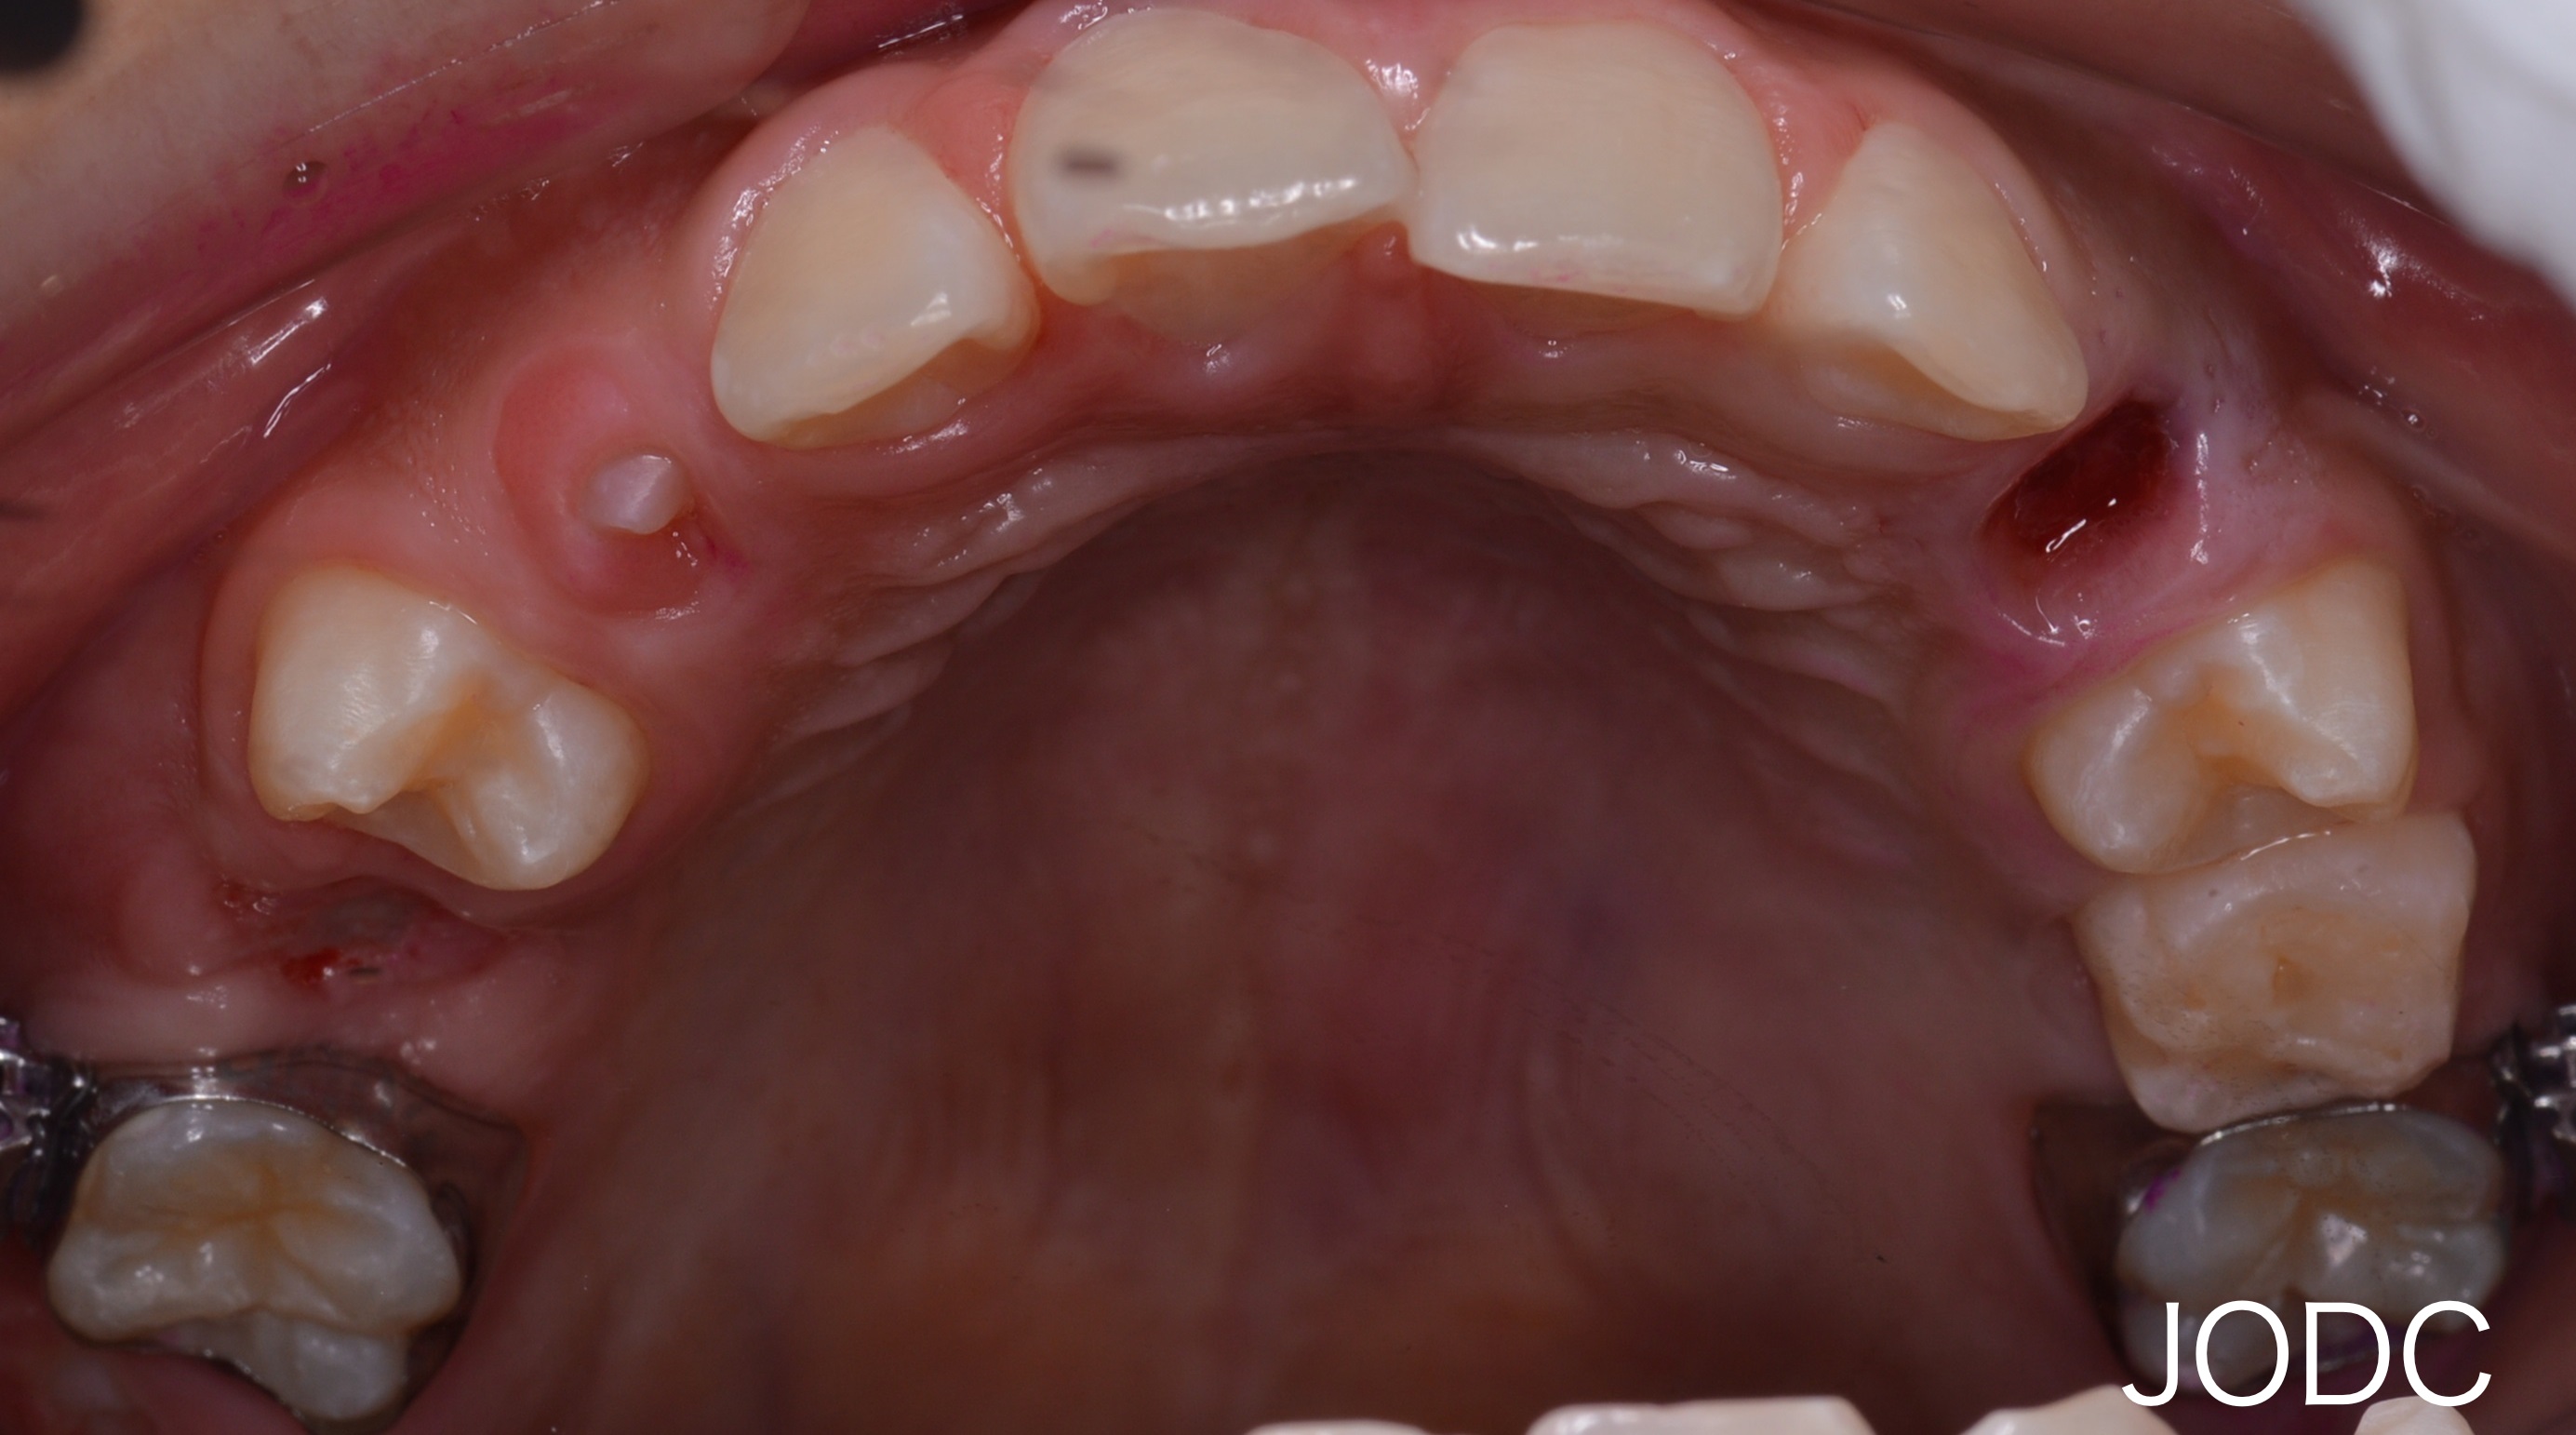

【2】カリエール

上顎前突「出っ歯」の改善を目的とする装置で、上顎左右犬歯から大臼歯を遠心移動する為に使用します。

“カリエール”を口腔内に装着し、下顎左右第一大臼歯の装置とカリエールに顎間ゴムをかけます。

顎間ゴムをかけることで上顎は後方へ、下顎は前方へ誘導される力がかかります。この作用で上下顎の顎関係の改善をはかります(After写真は約1ヶ月後)。

犬歯から第一大臼歯にかけて遠心移動し、上下顎がしっかり咬み合う所まで誘導できました。カリエールを装着する事で後の矯正治療で行うブラケット装置での治療期間を短縮することができます。